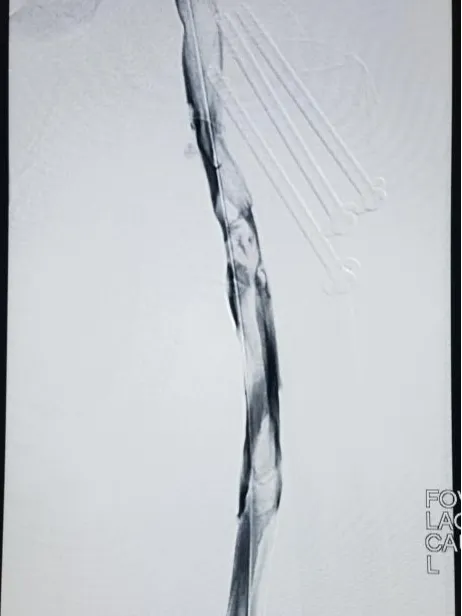

患者因左下肢进行性高度肿胀10天入院,行下肢静脉超声提示:左下肢深静脉多发血栓形成,术前下肢顺行静脉造影见:左下肢深静脉见广泛充盈缺损,血栓负荷重,血流严重受阻。 术前髂、股静脉大量血栓   为避免患者发生致命性肺栓塞,快速减少血栓负荷,介入血管外科黄云主任医师团队予DVT的“一站式治疗"介入手术治疗,手术过程顺利,患者术后左下肢肿胀迅速缓解。 术后造影股浅静脉血栓消失 患者术前术后患肢对比图 DVT(下肢深静脉血栓)的危害 01 肺栓塞(PE)占院内死亡的1/10; 02 2/3的静脉血栓栓塞症(VTE)事件与DVT有关,其中80%为中央型DVT; 03 DVT发生后,6个月内复发的几率非常高; 04 血栓进展扩大,股青肿,严重者可致截肢; 05 反复出现的DVT; 06 远期危害PTS(下肢深静脉血栓后综合作,也称后遗症),经久不愈的老烂腿。 DVT的“一站式治疗" 静脉解决方案 混合型或中央型DVT患者,下腔静脉滤器置入(预防肺栓塞)+静脉血栓抽吸+髂总静脉支架成形(髂静脉卡压)一站式完成。 优点:可预防肺栓塞、快速有效降低血栓负荷、降低远端静脉压;有效降低股青肿截肢风险及PTS发生几率,远期效果良好,患者显著获益。 长治市第二人民医院介入血管外科是集门诊、病区、手术室为一体的完整临床学科,科室医技护共15人,其中主任医师1人,主治医师2人,医师1人,硕士研究生1人。2011年在我市率先引进(GE)数字平板血管造影机,目前已成为中国出血中心联盟理事单位、山西省外周介入专科联盟理事单位、山西省血管疾病专科联盟成员单位、河南省门静脉专病疾病联盟单位等。从2012年至今共完成放射介入及外科手术数千余台,为胸痛中心、脑卒中中心开通绿色应急通道,争分夺秒抢救危重患者付出一份力量。 介入血管外科先后与北京协和医院、北京天坛医院、郑州大学第一附属医院、山西医科大学第一医院等省内外知名医院形成良好的协作关系。经过十余年的发展,我科已经形成神经介入、肿瘤介入、外周血管介入、综合介入、外科手术等较完备的诊疗体系。 联系电话 黄云主任:15635582732 段涛副主任:15635580757 专家简 黄云   主任医师 介入血管外科主任 先后在北京协和医院、北京医院、郑州大学第一附属医院进修学习,从事放射影像诊断与介入治疗工作二十余年。擅长各类良恶性肿瘤、下肢深静脉血栓与肺栓塞、各类出血性疾病、缺血性脑血管疾病、糖尿病足、肝硬化门脉高压、动静脉狭窄及闭塞、消化道(食道、贲门幽门、十二指肠、结肠)梗阻、梗阻性黄疸、各脏器脓肿及囊肿等疾病的影像诊断与介入诊疗,并擅长CT引导下经皮肺穿、肝穿、肾穿等综合介入诊疗技术。主编影像诊断与介入治疗专著一部,在省级以上医学期刊发表论文十余篇。 山西省医学会介入医学专业委员会委员、山西省医学会血管外科专业委员会委员、山西省医师协会介入医师分会常委、山西省医师协会肿瘤消融专业委员会常委、山西省抗癌协会肿瘤介入专业委员会委员、山西省抗癌协会肿瘤消融专业委员会常委、山西医学会血管外科分会静脉血栓与肺栓塞防治学组委员、山西省医师协会介入医师分会长治学组副主任委员、长治医学会介入医学专业委员会副主任委员。 专家简 段涛 副主任医师 外科学硕士 介入血管外科副主任 围血管疾病的开放、腔内治疗及下肢静脉曲张的微创治疗。 【学术任职】 曾先后在先后在西京医院、郑州大学第一附属医院、北京安贞医院学习,主持山西省科技厅青年项目一项,参与国家自然科学基金研究一项、省级科研项目3项,发表SCI论文一篇(IF=2.975),在《中华肝胆外科杂志》、《中国普通外科杂志》等国家级期刊发表论文10余篇。 山西省抗癌协会肝癌专业委员会委员、山西省抗癌协会肿瘤消融专业委员会委员、山西省医师协会介入医师分会青年委员、山西省医师协会介入医师分会肿瘤专业委员会委员、山西省医师协会介入医师分会长治学组委员、长治市医师协会肝胆外科分会常务委员、长治市医学会介入专业委员会委员。      供   稿丨黄 云 贾 岛 编   辑丨张静晗 审   核丨雷   赫